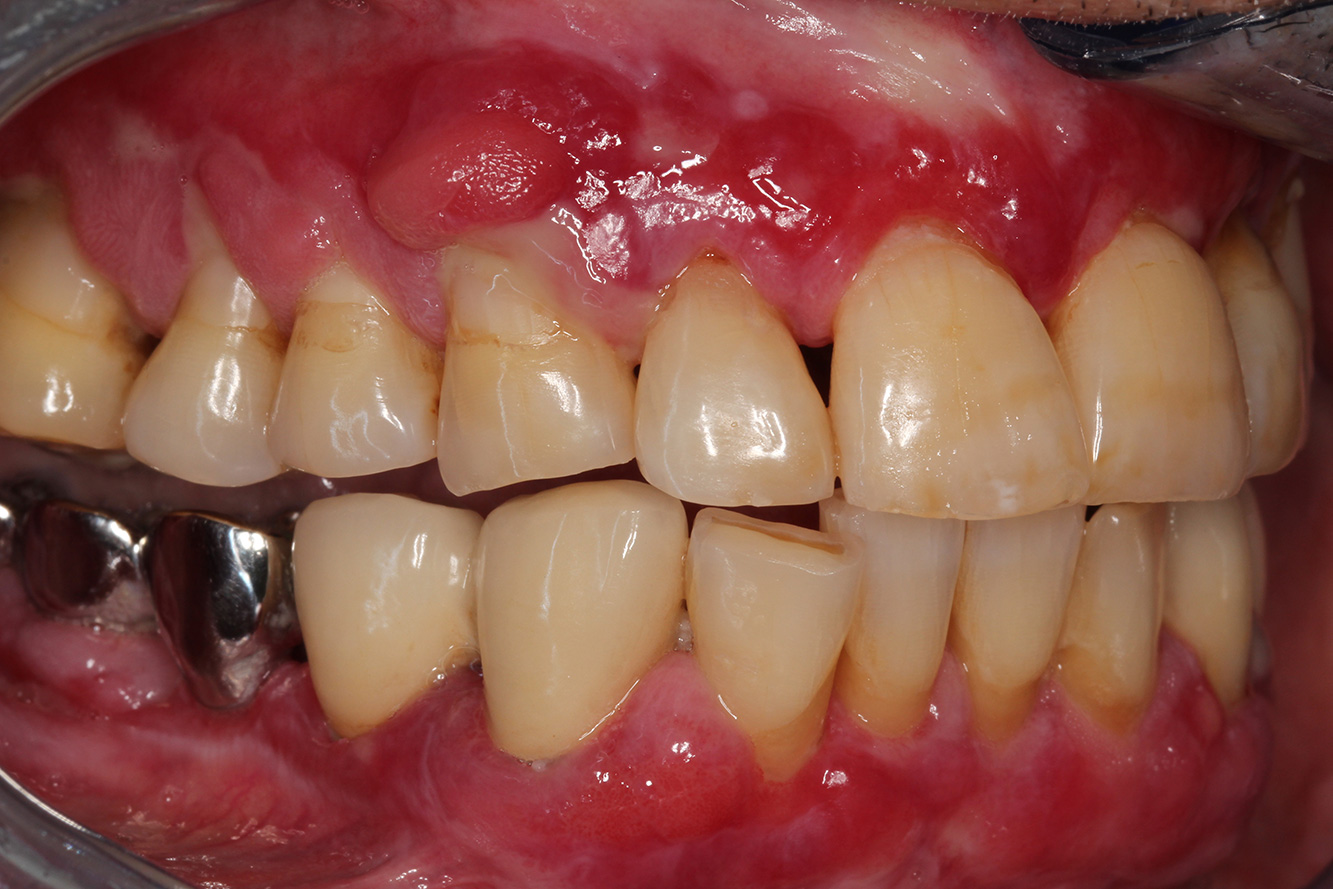

Si presenta un paziente di 71 anni che ha subito un trapianto di reni e con anamnesi di ipertonia (ipertensione). Considerata la sua storia clinica, serve una terapia a lungo termine con ciclosporina che ha un effetto immunosoppressivo e amlodipina che è specifica contro l'ipertensione. Il paziente riporta anche gengive sensibili e sanguinanti. Per quanto riguarda invece lo stato di salute orale, il paziente ha un restauro, presenta un'iperplasia gengivale marcata, una parodontite allo stadio II, grado B con tasche attive e un'iniziale carie radicolare al dente 22 e in più mancano otto denti. Dalla valutazione del rischio di carie si evince un rischio moderato di carie (API 60). Per la seduta di profilassi si possono formulare i seguenti consigli per il trattamento.

Sulla base dell'anamnesi del paziente si può rilevare un rischio particolare di complicazioni. Il paziente è immunodepresso (ciclosporina) in seguito al

trapianto di reni, quindi ha un sistema immunitario debole e necessita di una profilassi contro le infezioni (raccomandazione: 2 g di amoxicillina come antibiotico un'ora prima della seduta). Al tempo stesso, la terapia a lungo termine del paziente si traduce in un rischio aumentato di malattia, perché l'iperplasia gengivale riscontrata è associata proprio a questa terapia (20).

Bisogna quindi affrontare la situazione del paziente, in particolare per quel che riguarda training e istruzioni. Il paziente ha difficoltà a seguire una

corretta igiene orale a casa per via dell'iperplasia gengivale. Bisogna quindi parlare in modo chiaro con il paziente della sua maggior esposizione

alle infezioni così come della progressione e della ricomparsa dell'iperplasia (22). Al tempo stesso, bisogna istruire il paziente circa le tecniche di igiene

orale adatte per le sue esigenze specifiche.